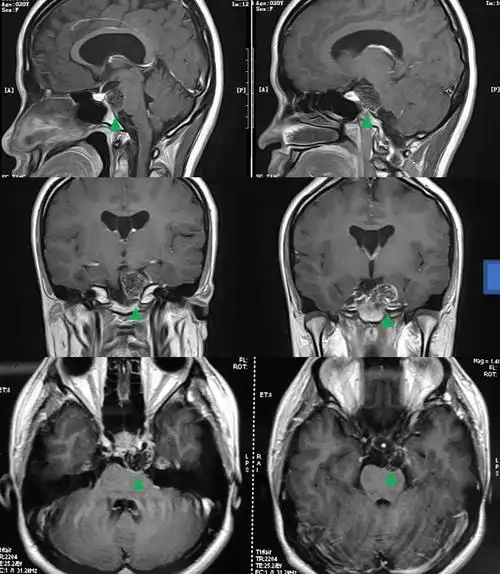

垂体肿瘤压迫视神经导致双眼近乎失明,鼻内镜下微创切除后视力恢复

垂体磁共振影像解剖

脑垂体的核磁共振检查结果请分析